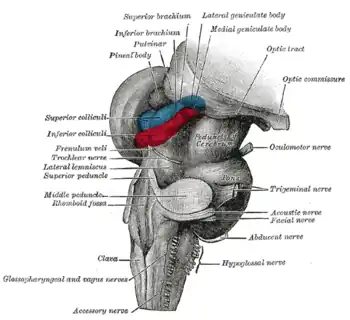

Cerebro anterior y medio. Vista posterolateral.

Cerebro anterior y medio. Vista posterolateral. Figura que muestra el modo de inervación de los músculos Recti medialis y lateralis del ojo.